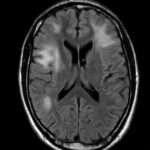

Cuando los tratamientos empíricos no tienen éxito, se puede considerar realizar pruebas adicionales, como manometría de pH, endoscopia, trago de bario, tomografía computarizada de senos paranasales o tomografía computarizada de alta resolución del tórax, para identificar la causa subyacente de la tos crónica